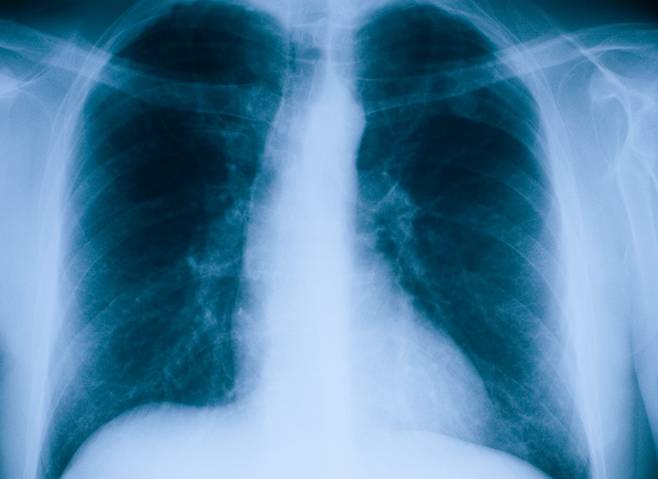

학술지 ‘The Indian Journal of Chest diseases& aliied Sciences’에 게재된 한 사례에 따르면, 인도 한 20대 여성은 기침, 가래, 발열 등의 증상이 시작돼 병원을 찾았다. 이 여성은 당시 병원에서 결핵 판정을 받고 항생제를 처방받았다. 그러나 병원 방문 후 약 4개월간 항생제를 복용했는데도 증상이 호전되지 않았다. 이후 여성은 다시 병원을 방문해 추가적인 검사를 받았다. 결핵 검사를 진행했을 때 여성은 음성 판정을 받고, 의료진은 여성의 폐를 스캔해보기로 결정했다. 그 결과, 여성의 폐에서는 거꾸로 뒤집힌 주머니 모양의 물체가 발견됐다.

의료진은 기관지 쪽에 있는 이 물체가 콘돔인 것을 확인했다. 여성과 그의 남편은 “부부관계 중 들어간 것 같다”고 의료진에게 전했다. 의료진은 콘돔에 사용되는 고무가 매우 부드럽고 유연하기 때문에 폐에 심각한 손상을 입힌 가능성은 적다고 판단했다. 그러나 숨을 마시고 내쉴 때마다 콘돔이 움직여 기침, 분비물 등을 유발한 것으로 보인다고 전했다. 이후 의료진은 기관지 내시경을 통해 콘돔을 제거했다.